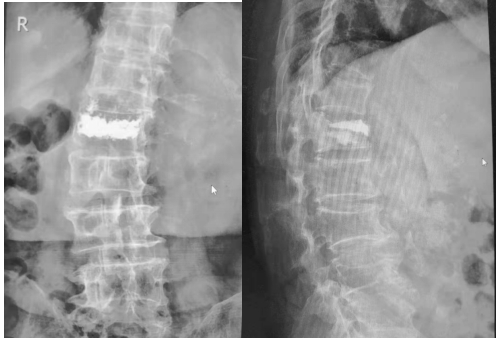

骨質(zhì)疏松性骨折椎體成型術(shù)后: